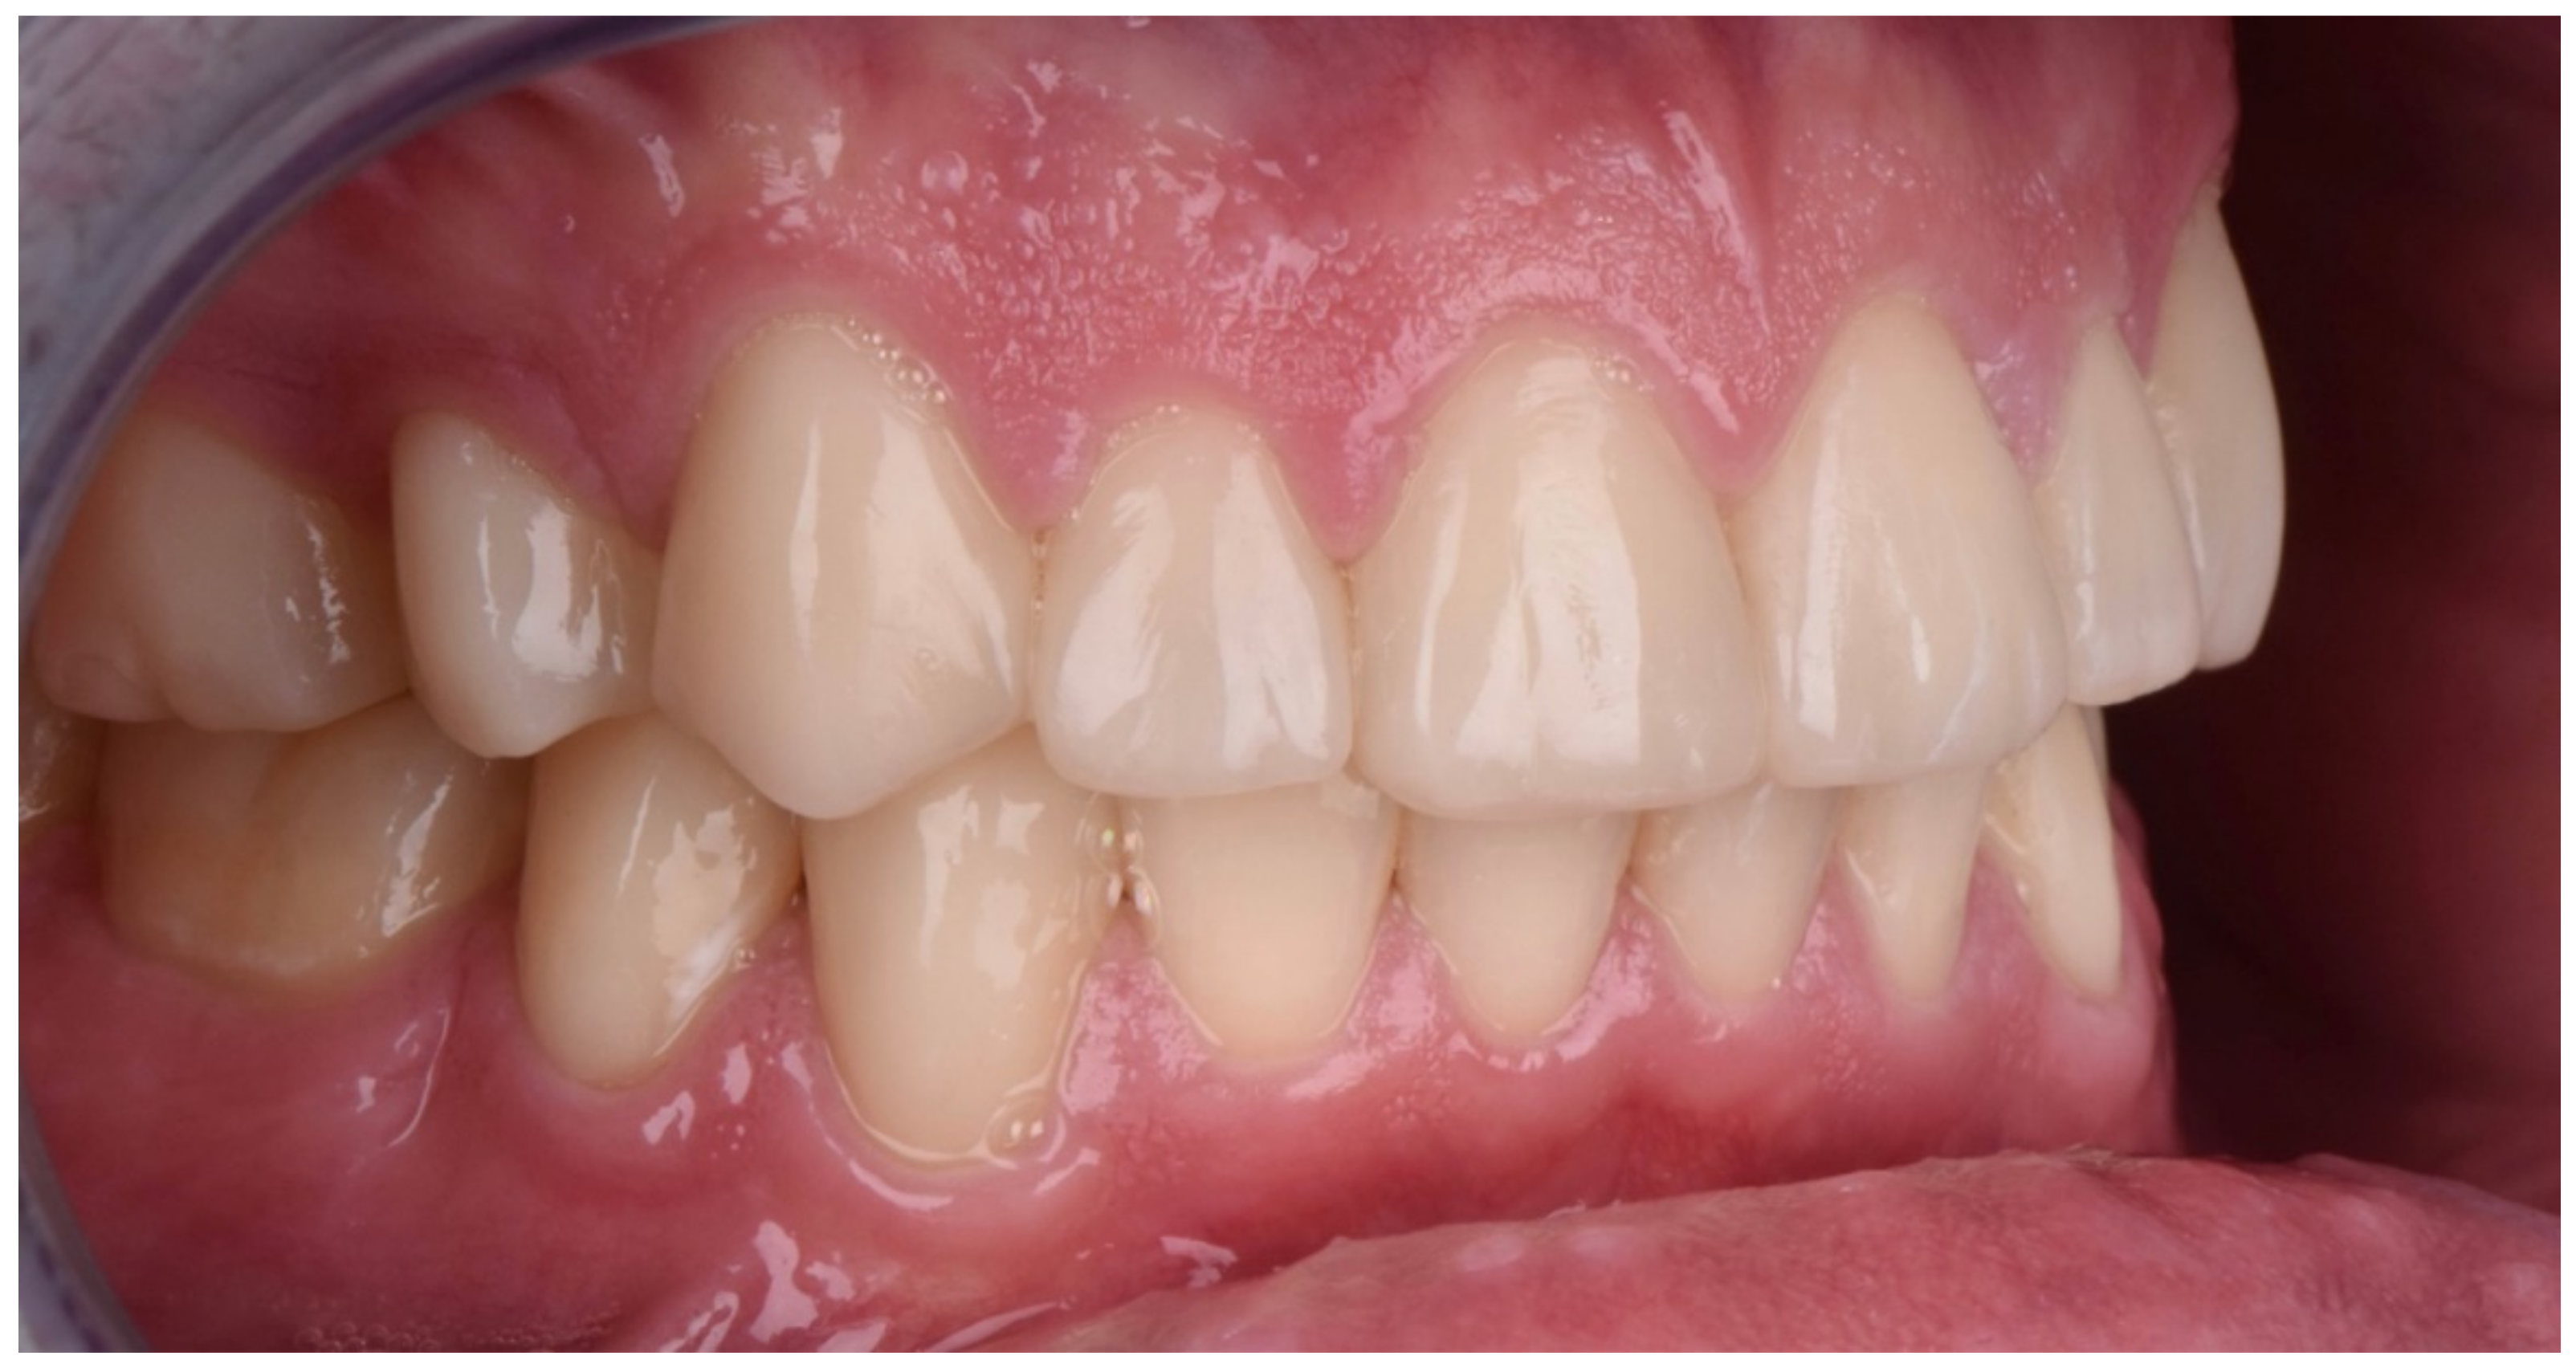

2.2. Restorative Phase